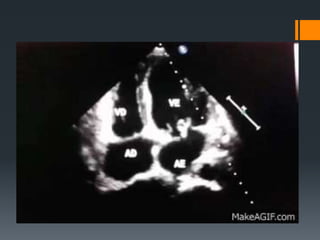

 Comprovativos de repercussões cardíacas

 ECG

 ECOCARDIOGRAMA

 Transtorácico sensibilidade de 40%

 Transesofágico sensibilidade de 90-100%